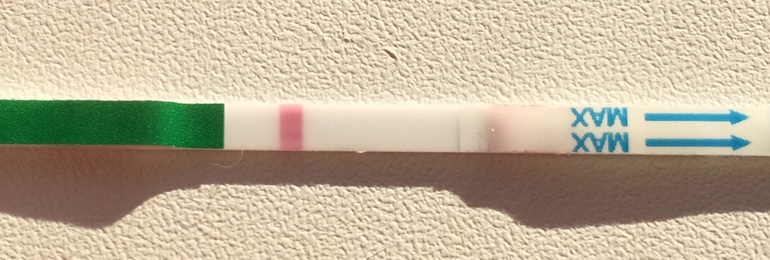

Вот сейчас вообще вижу 2 тоненьких полоски, как очертания жирной одной. Я одна такая ?или глючит?

А может это колективная галлюцинации:-D Когда следующий тест? Я в предвкушении

А вот и узнаем скоро, а тест какой? У меня тест через 10 часов среагентил:-) так что жду твоих и моих полосок

Вот я ни разу не видела реагенты, хотя беру тоже дешевые,тут в Но можно разориться на тестах:-) Еще тут на бб куча историй про 8 дпо с полоской, и самые дешевые тесты самые первые показывают. Поройтесь в копилке тестов.